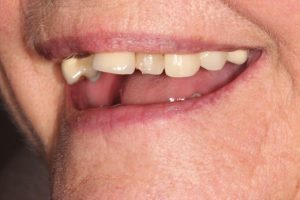

Upper Front Tooth Implant

This patient had broken their upper front tooth and the exisitng dental crown had fallen off. The underlying root was unfortunatley irreparable.

The dental root was subsequently removed and an implant placed at the same time. The implant had a temporary crown placedon the same day.

The ‘After’ photos shows the final crown that was made after 3 months. The implant crown was made to match the form and colour of the exisiting teeth to give an overall natural aesthetic finish.